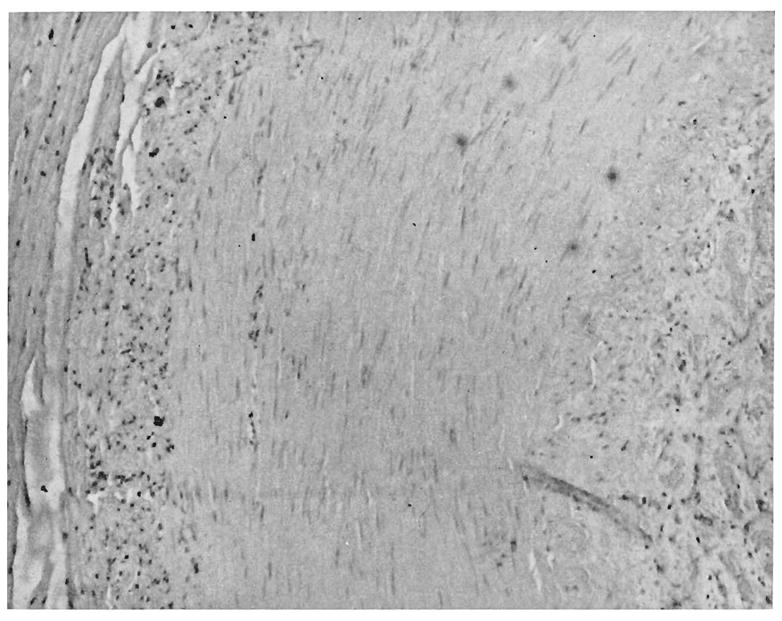

Changes in small blood vessels are obvious promptly with thawing. Using microangiography and transillumination techniques, these may evolve for weeks or months.5 There is an immediate, intense arterial vasoconstriction at the junction of uninvolved tissue with frozen tissue. Within a few hours, a demonstrable increase in vascularity occurs in the marginal zone, at the time this area becomes clinically erythematous. Some authors have described the opening of small arteriovenous shunts in this region.20 Flow rate is reduced and intravascular sludging is observed. Within three days multiple small areas of stenosis, or frank, sharply delineated occlusions have been observed microangiographically5 within the previously-frozen area. Tubular filling defects which are thought to be thrombi can be demonstrated in both arteries and veins. By the tenth day these either regress or proceed to stenosis or occlusion of the vessels. During the ensuing weeks, both arteries and veins disappear from the microangiography pattern, presumably due to late thrombosis. The resulting destruction of vascular architecture is partially compensated by the previously mentioned increase in marginal blood supply from which new branches may bud into the formerly frozen area.6 However, in six to twelve weeks such new networks undergo involution and, if the injured area does not undergo necrosis, it is left with a distorted and cross-sectionally reduced vascular pattern.5 Histologic sections at various stages in the above sequence show edema and small-vessel thrombi which are often fibrinoid in character (Fig. 5), and later areas of local arteritis or intimal proliferative thickening (Fig. 6).

Fig. 6.

Arterial injury, 11 months following 2° frostbite. Note fibrous intimal proliferation and perivascular lymphocytic infiltration (Case IX). Lumen is on the right.

Case IX (CGH, 37387). A 57 year old white man sustained a minor exposure to cold 11 months following a second-degree frostbite of both feet. He suffered increasing causalgic-type symptoms in both feet following the second exposure. There was dependent cyanotic rubor and hyperhydrosis. These symptoms were relieved by lumbar sympathectomy. In addition, the distal phalanx of his fourth toe was amputated because of vascular insufficiency. The arteries in the toe were seen to contain fibrous internal proliferation, with perivascular lymphocytic cuffing as evidence of a long-standing, low-grade vasculitis (Fig. 6).